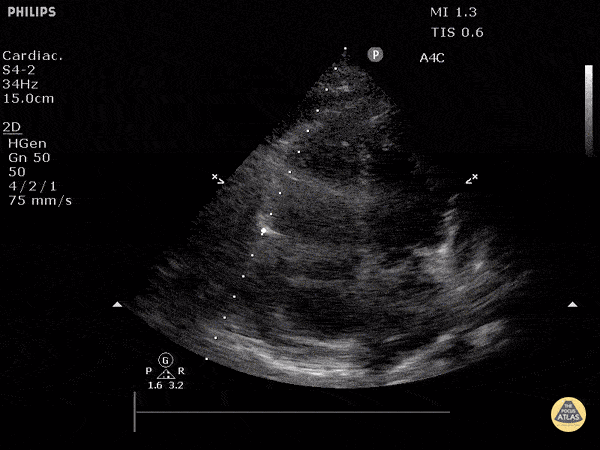

Pericardial Disease - Cardiac Tamponade in Apical View

Apical view demonstrating rocking heart with diastolic collapse of RV free wall. Justin Bowra MBBS, FACEM, CCPU Emergency Physician, RNSH et al. (Dr. Orr)